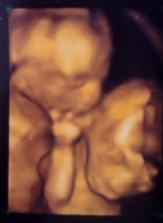

ahoj krasny album,môžem vedieť kedy ti zistili pohlavie ? a kedy si mala pohyby ?aj my čakáme dvojky...: -)